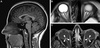

9

Q

HIPOTENSÃO INTRACRANIANA

- Quais os achados da RNM?

A

Espessamento da paquimeninge: principalmente

Aumento da hipófise

Derrame subdural

Redução da distância mamilopontina

Achatamento do tronco encefálico

MNEMONICO:

S: subdural fluid collections

E: enhancement of the pachymeninges

E: engorgement of the venous sinuses

P: pituitary hyperemia

S: sagging brain

How well did you know this?

Ataques frequentes* e incapacitantes

*>2 ou 3 dias por semana por 6 - 12 meses